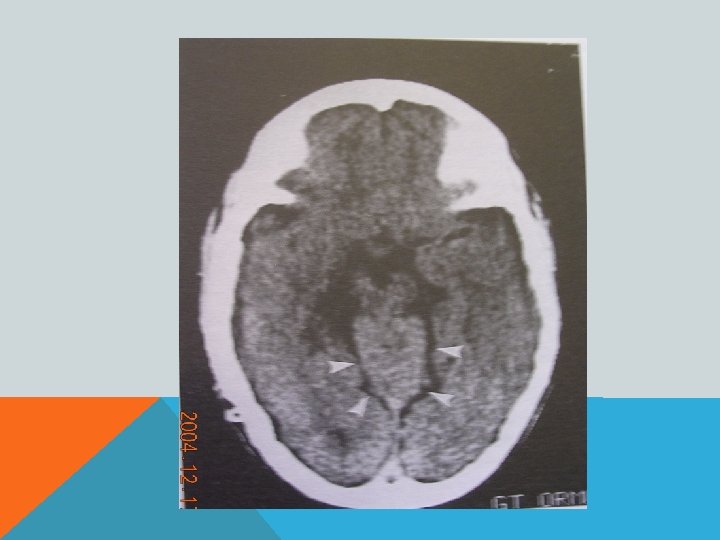

ПОРОК АРНОЛЬДА-КИАРИ 1 Увеличение миндалин мозжечка, их опущение в большое затылочное отверстие и далее, в спинномозговой канал- «нижний» вариант. Характерно образование сирингомиелической полости в шейном отделе спинного мозга. Основные клинические проявления- сирингомиелия.

ПОРОК АРНОЛЬДА-КИАРИ 1 Увеличение горки червя мозжечка и его смещение в межножковую цистерну- «верхний» вариант. Основные клинические проявления- расстройство равновесия (головокружение? )

ПОРОК АРНОЛЬДА-КИАРИ 2 Увеличение миндалин мозжечка, их опущение в большое затылочное отверстие и далее, в спинномозговой канал. «Щелевидный» 4 -й желудочек. Гипоплазия подушки моста мозга. Гипо-/аплазия мозолистого тела. Сирингомиелическая полость в шейном отделе спинного мозга. Фенестрация фалькса (серпа мозга) и т. д. В 70% сочетается со спинномозговой грыжей.